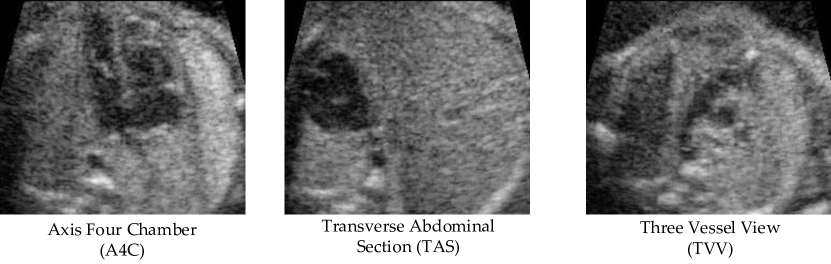

Refer to caption

Figure 3: Standard Planes

To evaluate the performance of the proposed embedded feature, a 4D STIC volume dataset is collected by Xinhua Hospital from GE E8 and the data is exported and stored in the DICOM format by 4DVIEW software from GE. The DICOM image has the size of four dimensions with three-dimensional structure and frame numbers (221×164×188221164188221\times 164\times 188 with 40 frames). To simplify the cases of disease, the volume data are divided into two parts with 92 normal cases and 93 abnormal cases. As shown in Figure 3, three standard planes including Four Chamber Section (A4C), Three Vessel View (TVV) and Transverse Abdominal Section (TAS) are selected for evaluations. For each volume, we uniformly generate 400 planes as candidate list and, for each standard plane, three candidates are labeled by expert as ground truth. In training step, we randomly select 46 normal cases and 46 abnormal cases from the full dataset. In testing step, we construct two evaluation settings: